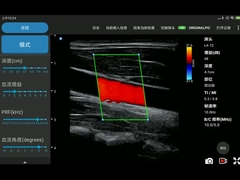

qualité Scanner tenu dans la main d'ultrason, Sonde sans fil d'ultrason fabricant de Chine

fournisseur de qualité Produits principaux